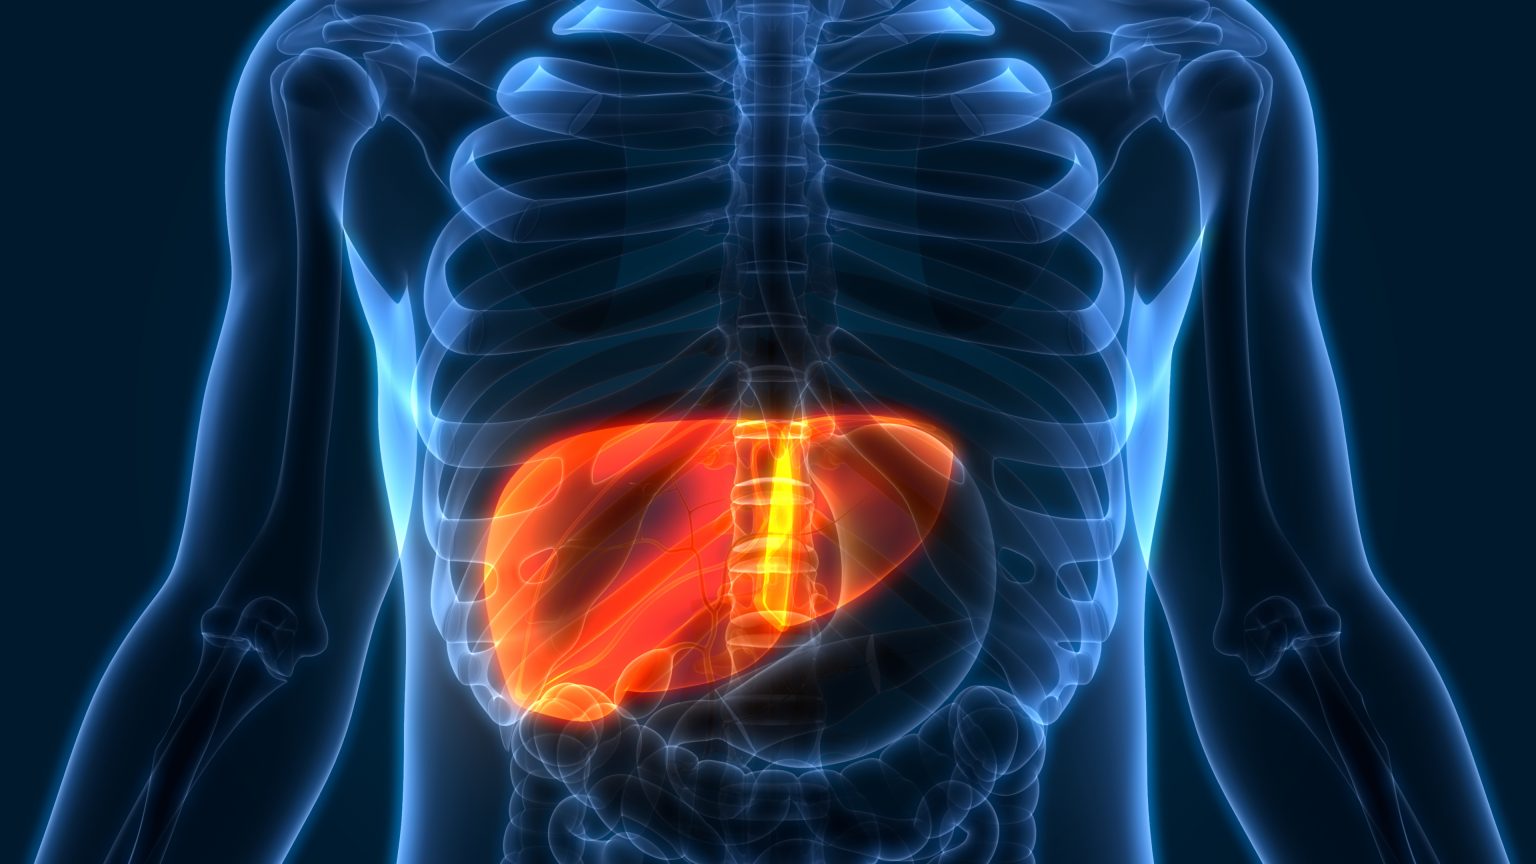

Картинки с надписью Liver: Как выбрать и использовать